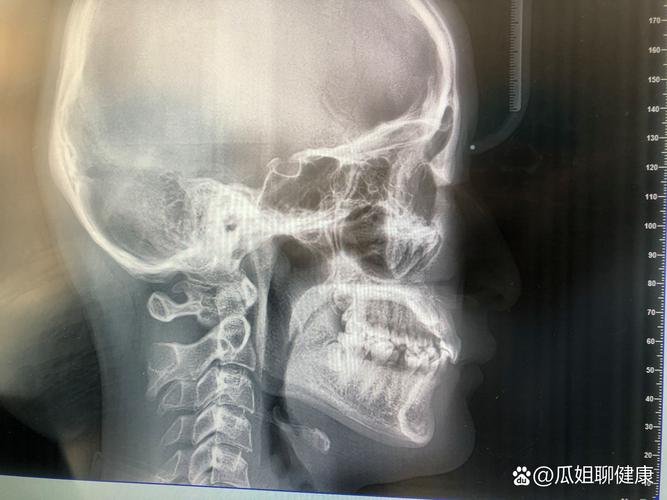

- 检查设备:CBCT(三维锥形束CT,用于骨量评估)、口内扫描仪(替代传统取模,避免恶心感)、数字化全景机(牙齿、牙根全景分析);

- 初诊:是否包含全面检查(口内检查、模型、X光片、头影测量等),而非简单看一眼就报价;